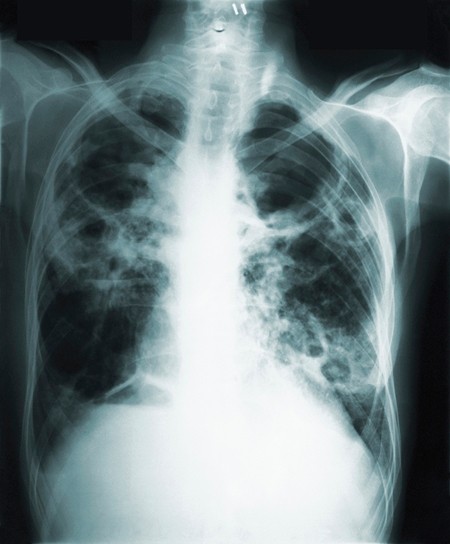

Doctors were encouraged because protection declined only a little after two years, and even a partially effective vaccine would be a big help against TB. The lung disease kills more than a million people a year, mostly in poor countries, and about one-third of the world’s people harbor the bacteria that cause it.

GlaxoSmithKline’s experimental vaccine was tested in nearly 3,600 adults in Kenya, South Africa and Zambia who were infected with TB but who did not also have HIV, the virus that causes AIDS.